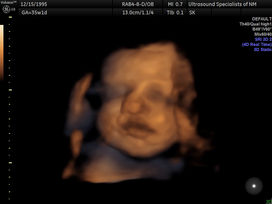

MomToBe3D4D offers the finest 3D / 4D / HD Live prenatal elective ultrasound experience available. Combining cutting-edge technology with a calming, comfortable environment, we bring unbelievable images of your unborn baby to life!

QUALITY Top of the line ultrasound equipment - GE Voluson E8 Expert with HD Live and Silhouette imaging

BEFORE

Add to your next 3D4D package

-

Bring life to your images

Professional digital editing

One image for $25 or two for $40

Already have your 3D images, no problem. You can email them to us and we can edit them.

8K image enhancements now available

AFTER